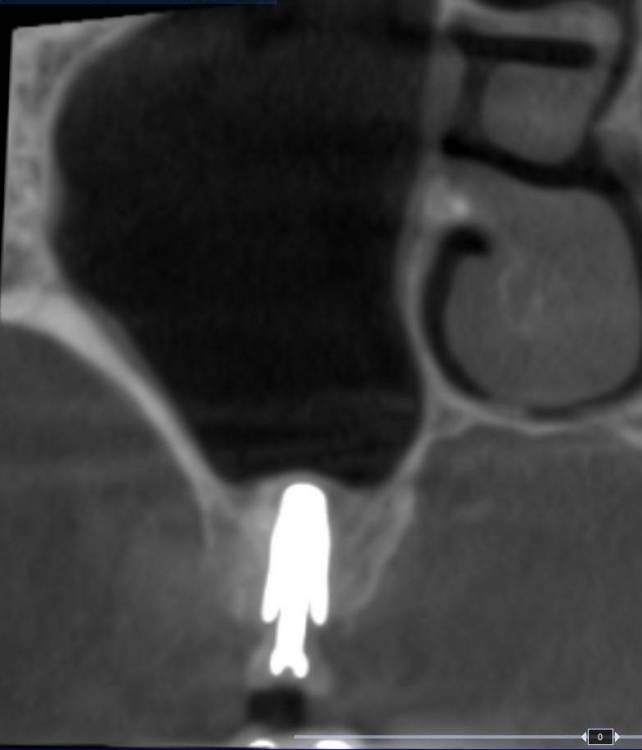

TIGER Опубликовано 9 марта, 2023 Автор Поделиться Опубликовано 9 марта, 2023 прошло 6 мес,кт 6 Ссылка на комментарий